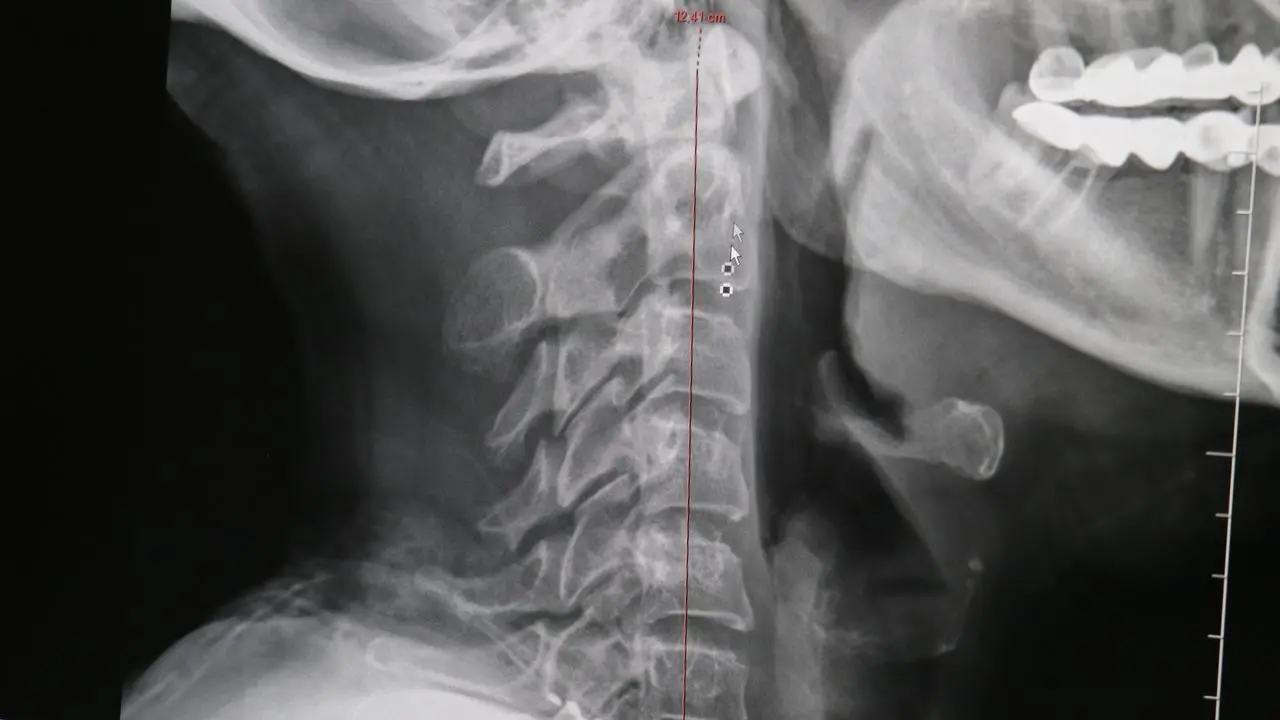

Boyun Düzleşmesi Ciddi Sağlık Sorunlarına Yol Açıyor

Teknoloji kullanımının artmasıyla her 10 kişiden 9'unda boyun düzleşmesi görülüyor. Bu durum ilerleyen dönemlerde felç riskini beraberinde getiriyor.

Boyun düzleşmesi önemli hastalıkların habercisi olabilir. Düzenli egzersiz ve doğru duruş pozisyonu ile bu sorunun önüne geçilebilir.